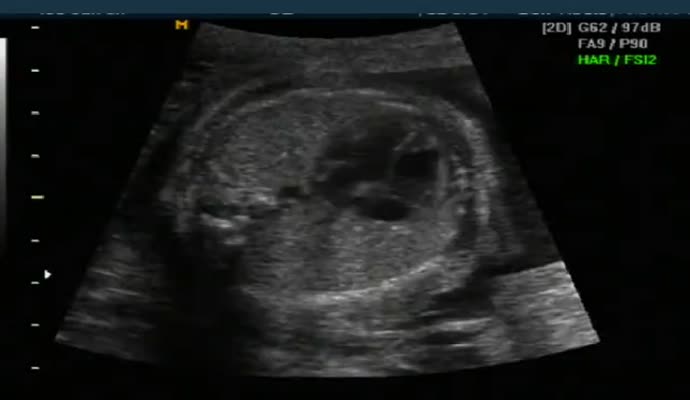

아래는 초음파 영상이기는 하지만 그렇게 올려진 영상 샘플입니다.

ob_usg_normal.mp4.jpg (17.74 KB, 다운수: 488)

ob_usg_normal.mp4

5.07 MB, 다운수: 878